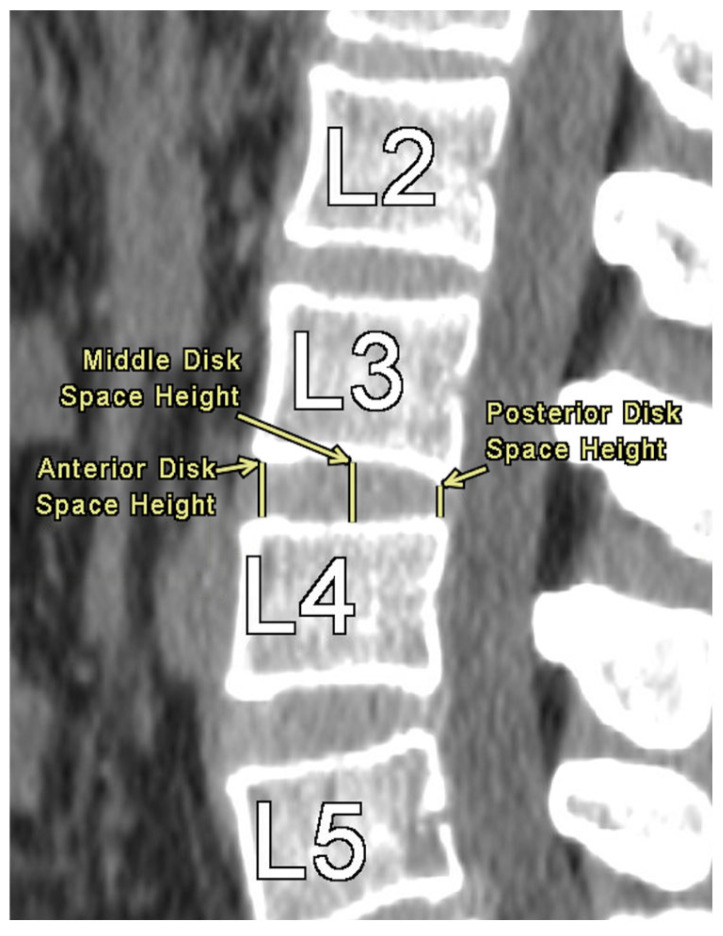

Methods: A retrospective chart review was performed on 852 patients who underwent CT imaging of the lumbar spine. ISD was measured from L1 to L5 as the shortest distance between the most caudal tip of the superior spinous process and the inferior spinous process. DSH was measured at the anterior, middle, and posterior margins. NFDs were assessed in axial and sagittal views, including axial width, craniocaudal height, and foraminal area. Statistical analysis assessed correlations between ISD, NFDs, DSH, and demographic variables.